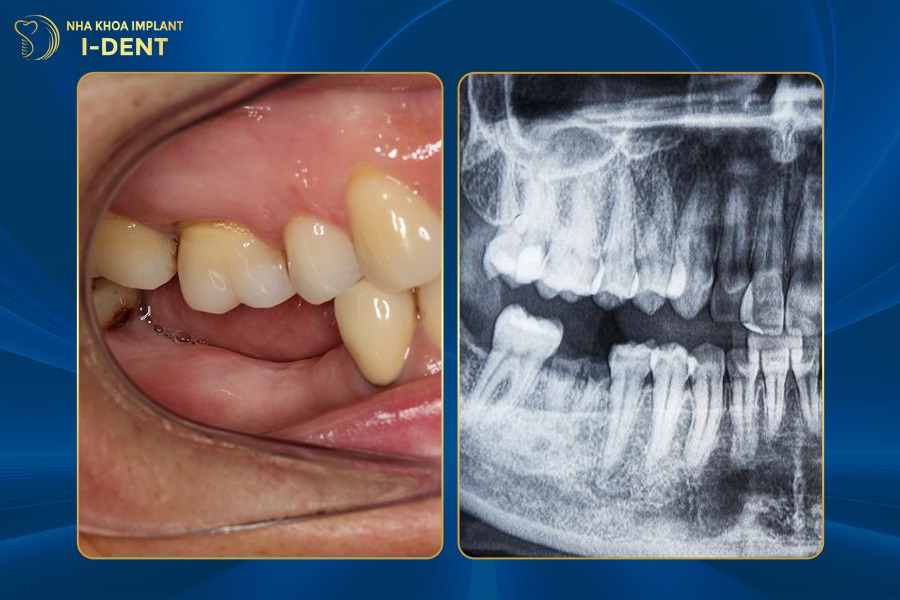

Tại Nha khoa I-Dent, bác sĩ luôn ưu tiên điều trị bảo tồn tối đa răng thật. Với những trường hợp mất răng nhưng chân răng còn khỏe thì bác sĩ sẽ giữ lại và phục hồi phần thân răng để duy trì cấu trúc xương hàm tự nhiên. Nếu bệnh nhân mất toàn bộ răng hoặc không thể giữ chân răng thì bác sĩ sẽ tư vấn phương pháp phục hình phù hợp đảm bảo kết quả ăn nhai tốt, thẩm mỹ tự nhiên và bền vững như răng thật.